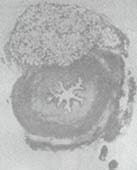

Desde la misma época, el uso de los derivados de la silicona comienza a popularizarse en especialidades como la cirugía plástica y la ortopedia con múltiples y exitosos empleos en el manejo de heridas, prótesis e implantes tisulares. El poli dimetil siloxano (MACROPLÁSTICO) es una molécula totalmente biocompatible carente de actividad alergénica conformada por partículas elastómeras sólidas de un diámetro promedio de 220 micrones, que hace prácticamente imposible su migración a sitios distantes debido a la dificultad que tendrían las células inflamatorias para fagocitarla y transportarla (figura No 1).

Figura No 1. Imagen de los implantes de macroplástico enel orificio ureteral. Es claramentevisible la superficie externa del

bolo y el material implantado estácompletamente encapsulado.